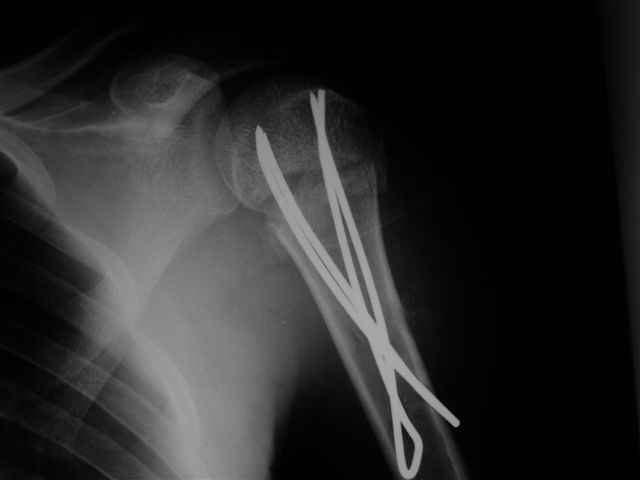

Re: Перелом шейки плеча

Посылаю послеоперационные Рг граммы.